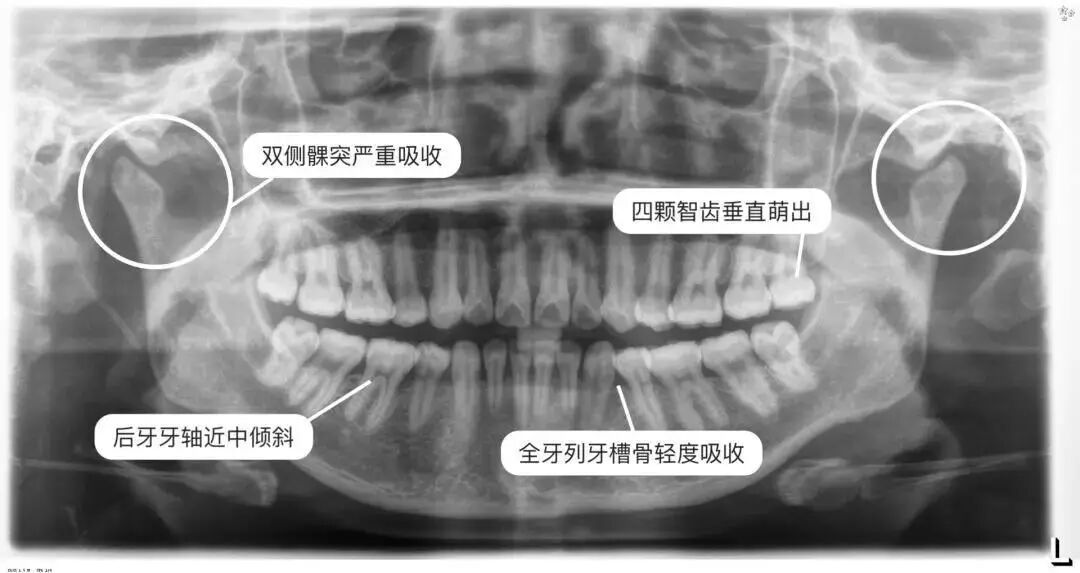

举个例子,下图这位大叔已经年过六旬了,大家可以注意到他的牙片。

曲面断层片怎么看科普知识:你会看牙片嘛?今天手把手教你看!_https://www.jmylbn.com_新闻资讯_第10张

可以看到牙周情况吗?

答:一般是可以的,通常来说,牙齿周围是被牙龈包裹没有很大缝隙的,如果口腔全景片上显示如下面这样的。

牙齿之间缝隙大而且是黑色阴影,牙齿整体比较长,多半是有牙周炎,牙槽骨情况也不好。(如下图)

被吸收的牙槽骨